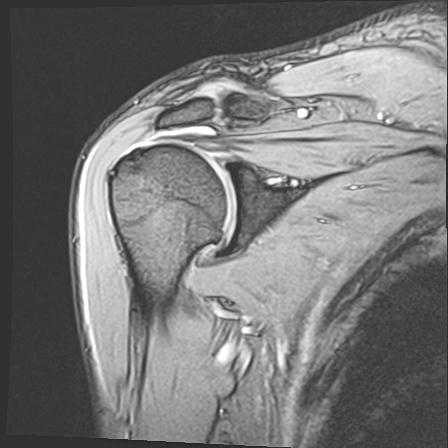

60058 3/9 11/4 右肩 2R+MRI 73歳男性 肩腱板損傷